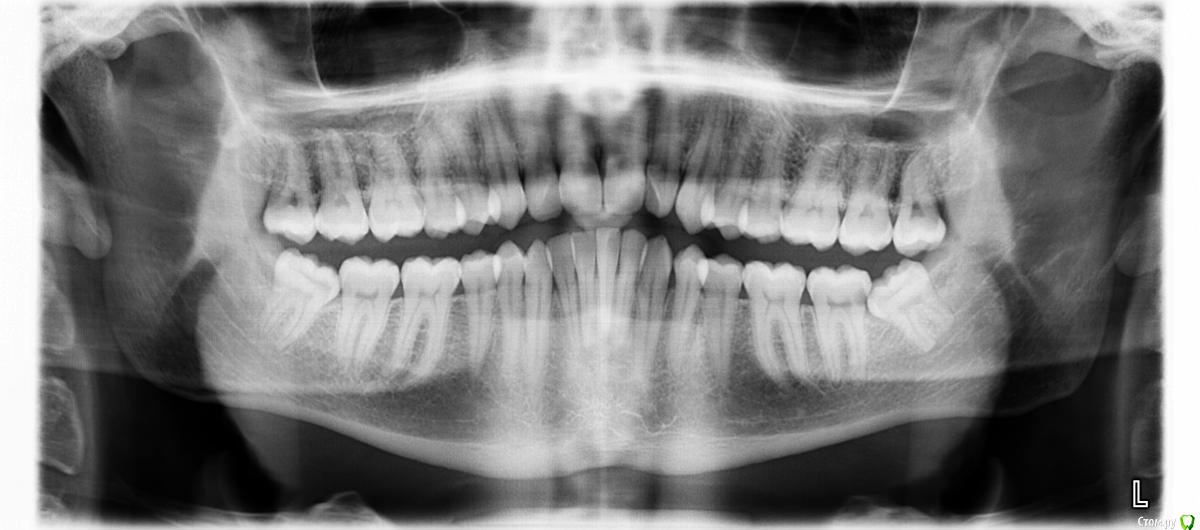

VasiliyM Опубликовано 1 февраля, 2015 Поделиться Опубликовано 1 февраля, 2015 Здравствуйте! У меня такая проблема: начали расти зубы мудрости в неправильном направлении, они растут под наклоном и упираются в зубной ряд. Давят на него, приносят болевые ощущения. Решил удалить их(нижние). Но тут есть еще такая проблема: я хочу в дальнейшем устанавливать брекеты, и у меня возникает вопрос, не требуется ли устанавливать брекеты не позднее определенного срока после удаления зубов мудрости? А то может быть после удаления зубов м. другие зубы без брекетов начнут заполнять освободившееся пространство и дальше для установки брекетов понадобится удалять нужные зубы. Подскажите пожалуйста что делать. И что вы можете еще сказать по поводу удаления зубов мудрости, насколько их необходимо удалять, и насколько это будет сложно?Панорамный снимок прилагаю прикрепленным файлом. Ссылка на комментарий

red_butler Опубликовано 2 февраля, 2015 Поделиться Опубликовано 2 февраля, 2015 удаляйте как можно скорее, на нижней челюсти слева на седьмом зубе похоже уже пульпит от мудрого Ссылка на комментарий

orthophil Опубликовано 4 февраля, 2015 Поделиться Опубликовано 4 февраля, 2015 Удаление зубов мудрости и начало ортодонтического лечения в Вашем случае не взаимосвязаны. Удаляйте сначала нижние, а потом обязательно верхние. В противном случае верхние восьмерки будут со временем опускаться и блокировать полноценное движение нижней челюсти.PS похоже и с правой нижней семеркой не все в порядке. Ссылка на комментарий